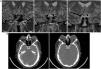

Se presenta el caso de un varón de 45 años con diagnóstico de acromegalia. La resonancia magnética identificó una marcada dilatación de ambas arterias carótidas internas (ACI) cavernosas con medialización de las mismas, condicionando una distancia intercarotídea estrecha, fenómeno conocido como «kissing carótidas».

Esta alteración vascular se ha descrito en mayor proporción en pacientes con acromegalia. Las anomalías que también se presentan con mayor prevalencia en estos pacientes son: aneurismas de la ACI, protrusión de la ACI en el seno esfenoidal, distancia intercarotídea estrecha, dilatación fusiforme de la ACI y la dehiscencia de tal arteria en el canal óseo. La presencial de tales alteraciones aumenta el riesgo de lesión de la ACI.

We present the case of a 45-year-old male diagnosed with acromegaly. Magnetic resonance imaging identified a marked dilatation and medialization of both cavernous internal carotid arteries (ICA), leading to a narrow intercarotid distance, a phenomenon known as “carotid kisses”.

This vascular alteration has been described in greater proportion in patients with acromegaly. The anomalies that are also present with greater prevalence in these patients are: aneurysms of the ICA, protrusion of the ICA into the sphenoid sinus, narrow intercarotid distance, fusiform dilatation of the ICA and dehiscence of this artery in the bony canal. The presence of such alterations increases the risk of injury to the ICA.